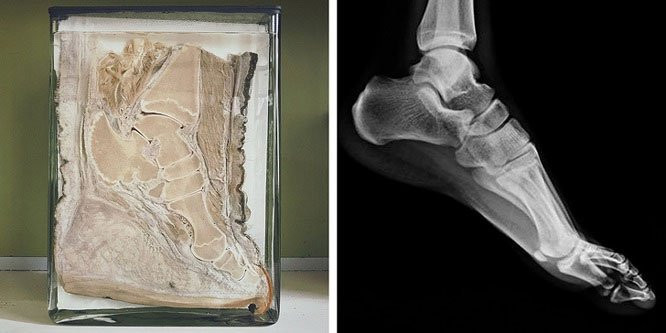

2. Chân voi có cấu tạo xương gần giống chân người. (Ảnh: BrightSide).